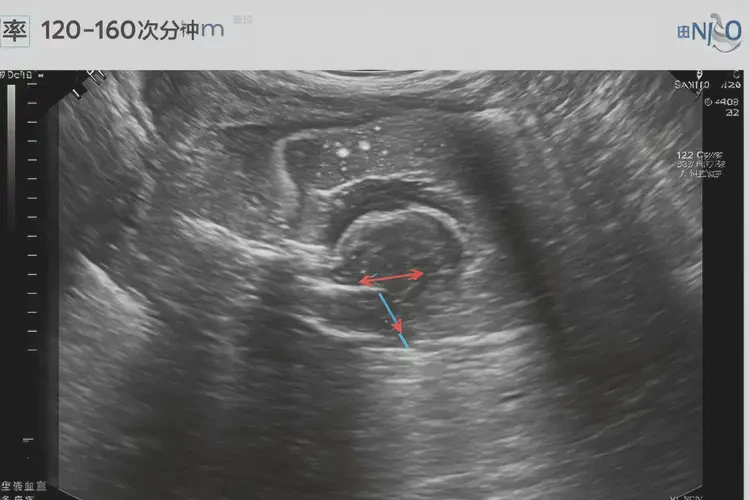

在怀孕第20周,胎儿的胎心率通常在120-160次/分钟之间。胎心率低于120次/分钟或高于160次/分钟都可能表示存在潜在问题。胎心101次/分钟明显低于正常范围,可能提示胎儿存在缺氧或其他健康问题。

以下是不同孕周胎心率的正常范围:孕周 正常范围(次/分钟) 12-16周 140-170 17-20周 120-160 21-24周 110-160 25-32周 110-160 33-36周 110-150 37周及以上 110-150 胎心率异常的可能原因